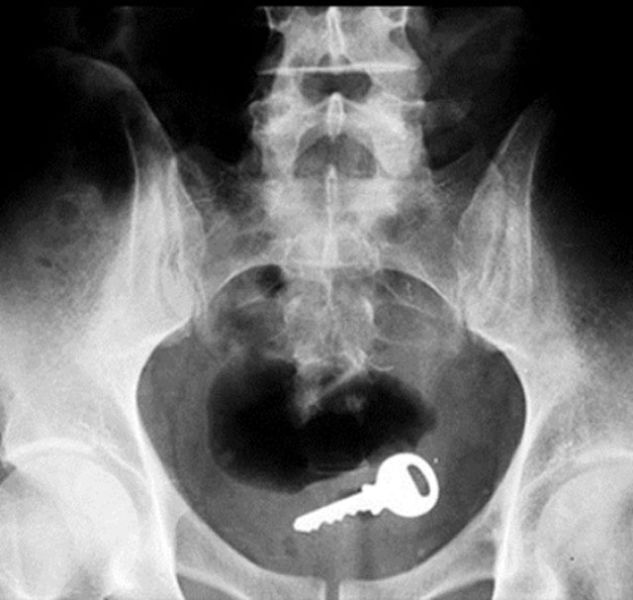

Key